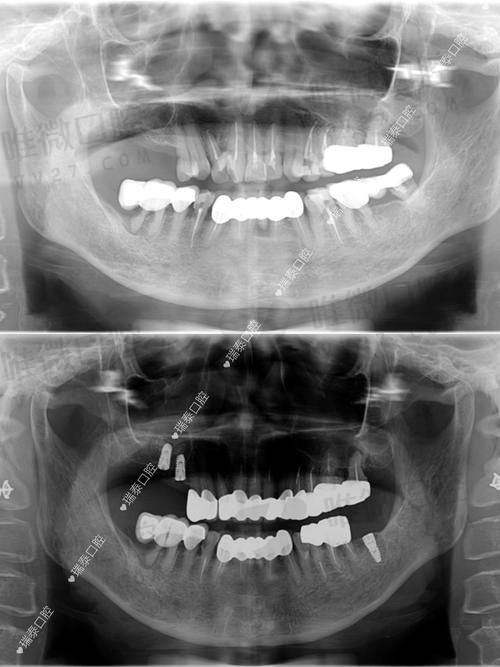

除了医生厉害,医院的设备咱也不能马虎。定靖口腔医院的设备可不是“凑合用”,而是非常现代化的。比如,医院目前配备了8台口腔综合治疗机、韩国怡友口腔全景影像设备、美国的根管测量仪与根管马达、德国进口的卡瓦光敏固化设备等等。

这些高端设备的加入,使得常规的拔牙、补牙到牙齿种植、正畸矫正治疗都变得更加效率高、精细和舒适。尤其是在进行根管治疗或者数字化正畸时,精良的设备真的能让你少遭不少罪。

尤其是他们家的数字化种植技术和活动义齿定制服务,已经逐渐成为区域内的小标杆。通过3D数字口扫+导板种植技术,不仅快捷、正确,还减少术后不适,是不少中老年患者的优选之一。